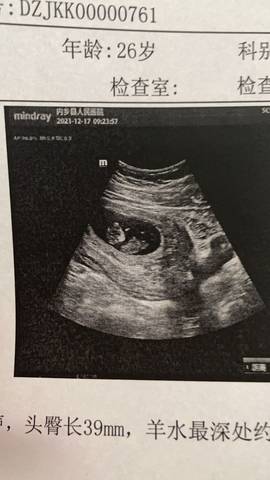

哈哈……好开心,今天我的崽11周啦……

可爱的甜甜 2021-12-17 11:33

#妈妈问答大赛#确实是值得高兴的日子,建议保持良好的心态,平时多加强营养哦